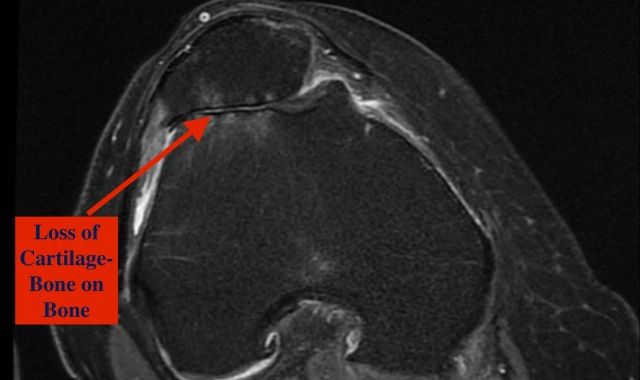

Adult Total Knee Replacements -

Unicompartmental Knee Replacement -